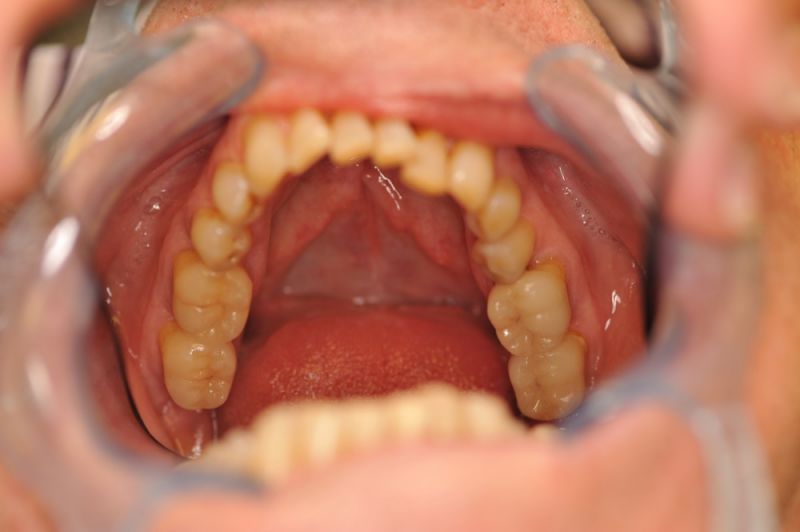

Alles siehgt perfgekt aus. 2 mm tiefe Taschen, perfekte Mundhygiene. Die Arbeit funktioniert!